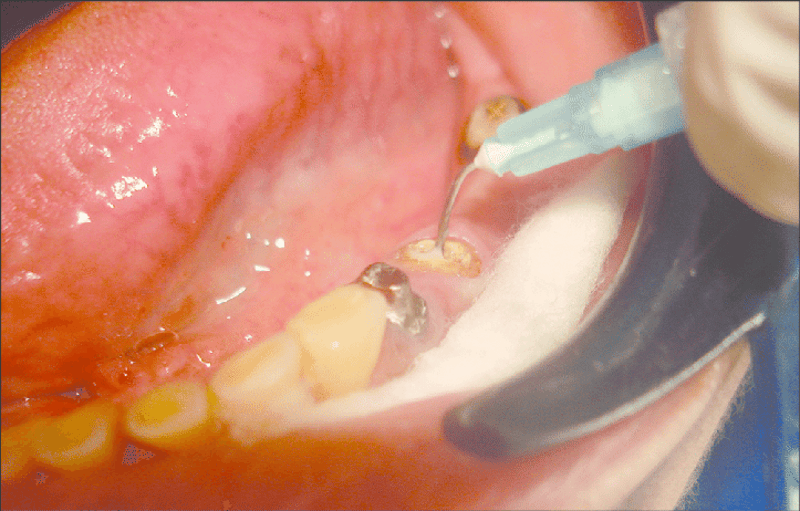

Máy rung rửa siêu âm đặc biệt hữu ích trong các trường hợp ống tủy phức tạp, ống tủy hẹp, ống tủy bị nhiễm trùng nặng. Trong các trường hợp này, các phương pháp rung rửa truyền thống thường không đủ hiệu quả, trong khi máy rung rửa siêu âm có thể giúp làm sạch ống tủy một cách triệt để.